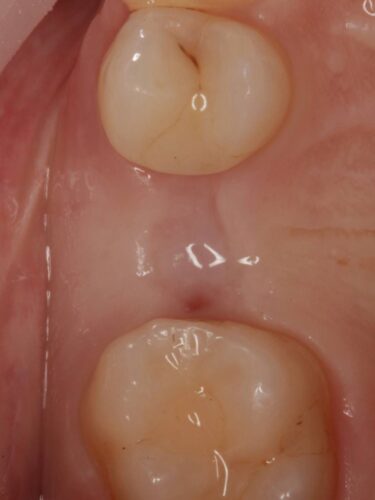

Установка импланта, подшит трансплантат с бугра( для увеличения объема мягких тканей), установлен формирователь десны